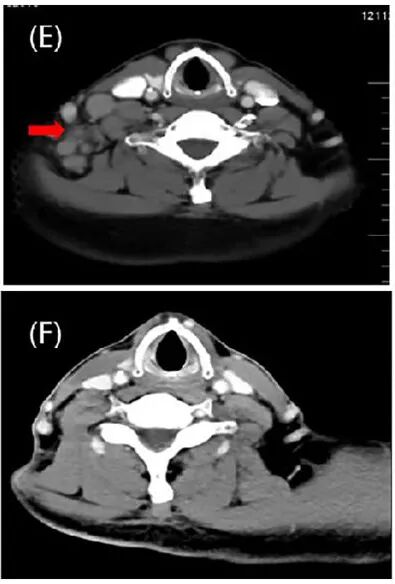

2021年10月,患者右侧颈后三角和右侧锁骨上多个淋巴结肿大(下图E)。

经MDT讨论,患者接受了颈部淋巴结放疗,共33周期。在放疗过程中,患者继续接受纳武利尤单抗维持治疗9个周期。CT结果显示,局部放疗后,颈部淋巴结转移灶表现为PR(下图F)。